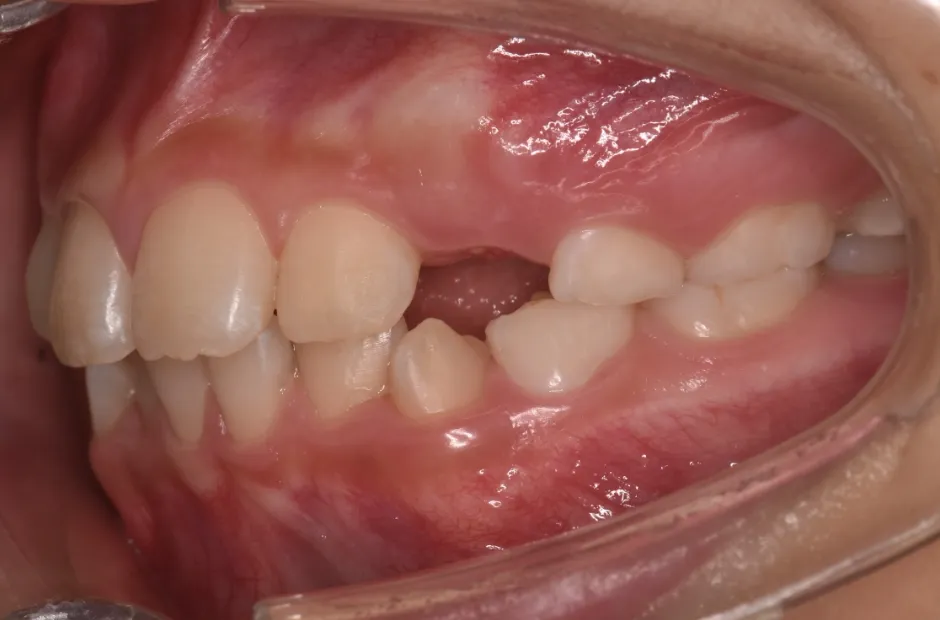

反対咬合

| 診断名・主訴 | 前歯反対咬合 |

|---|---|

| 年齢・性別 | 12歳・男性 |

| 治療期間・回数 | 1年半 18回 |

| 治療に用いた主な装置 | リンガルアーチ(前方誘導弾線) |

| 抜歯部位 | なし |

| 治療費 | 35万円(税抜) |

| リスク・副作用 | 装置による違和感・疼痛・歯肉退縮・歯根吸収・虫歯のリスクなど |

治療前